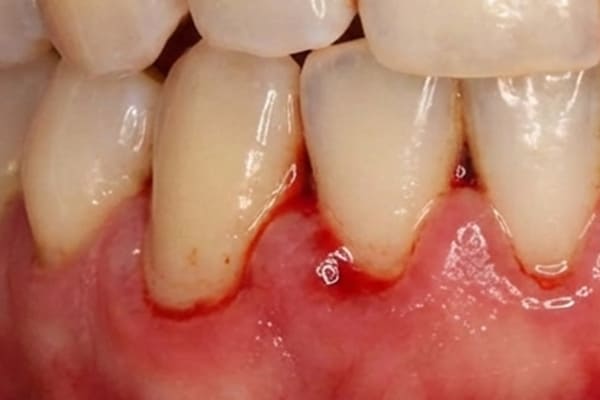

中度歯周炎 危険度★★★

中程度の歯周炎になると、口臭がおこり、歯茎が化膿します。ブラッシングをした際に膿がでることもあります。

歯周ポケットは4~5mm程度です。

この段階での治療法はスケーリングなどを使用して治療をしますが、歯周ポケットが5

mm以上深くなるとフラップ手術をする場合があります。フラップ手術は局所麻酔後、歯茎を切開し、隠れているプラークや歯石を取り除き、歯周病の進行を止める手術を行うことがあります。